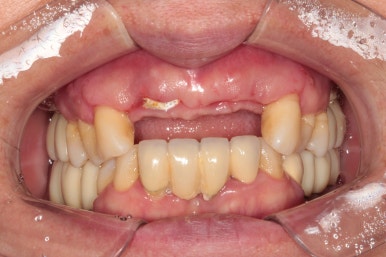

50대 여자 환자분입니다. 처음에 내원하셨을 때 정면 사진이에요.

딱 보아도 잇몸 상태가 참 좋지 않았습니다. ㅠㅠ 특히 위 앞니는 가만히 있어도 고름이 나오고 있는 상태지요..

만성치주염을 갖고 계신 환자분들은 이러한 상황을 조심하셔야 합니다.. 너무 방치되면 정말 임플란트를 심을 잇몸뼈가 하나도 남지 않을 수 있어요.... 그러다 진짜 틀니 하셔야 합니다!!...